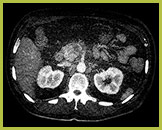

Badanie wykonane metodą „Virtual non-Contrast”

Utworzony przez usunięcie jodu z obrazu. Wykonane w jednostkach Hounsfielda (HU) pomiary na wirtualnych obrazach badania bezkontrastowego są w przypadku większości struktur porównywalne ze skanami wykonanymi bez środka kontrastowego, pozwalając zastąpić skany niekontrastowe obrazami VNC.